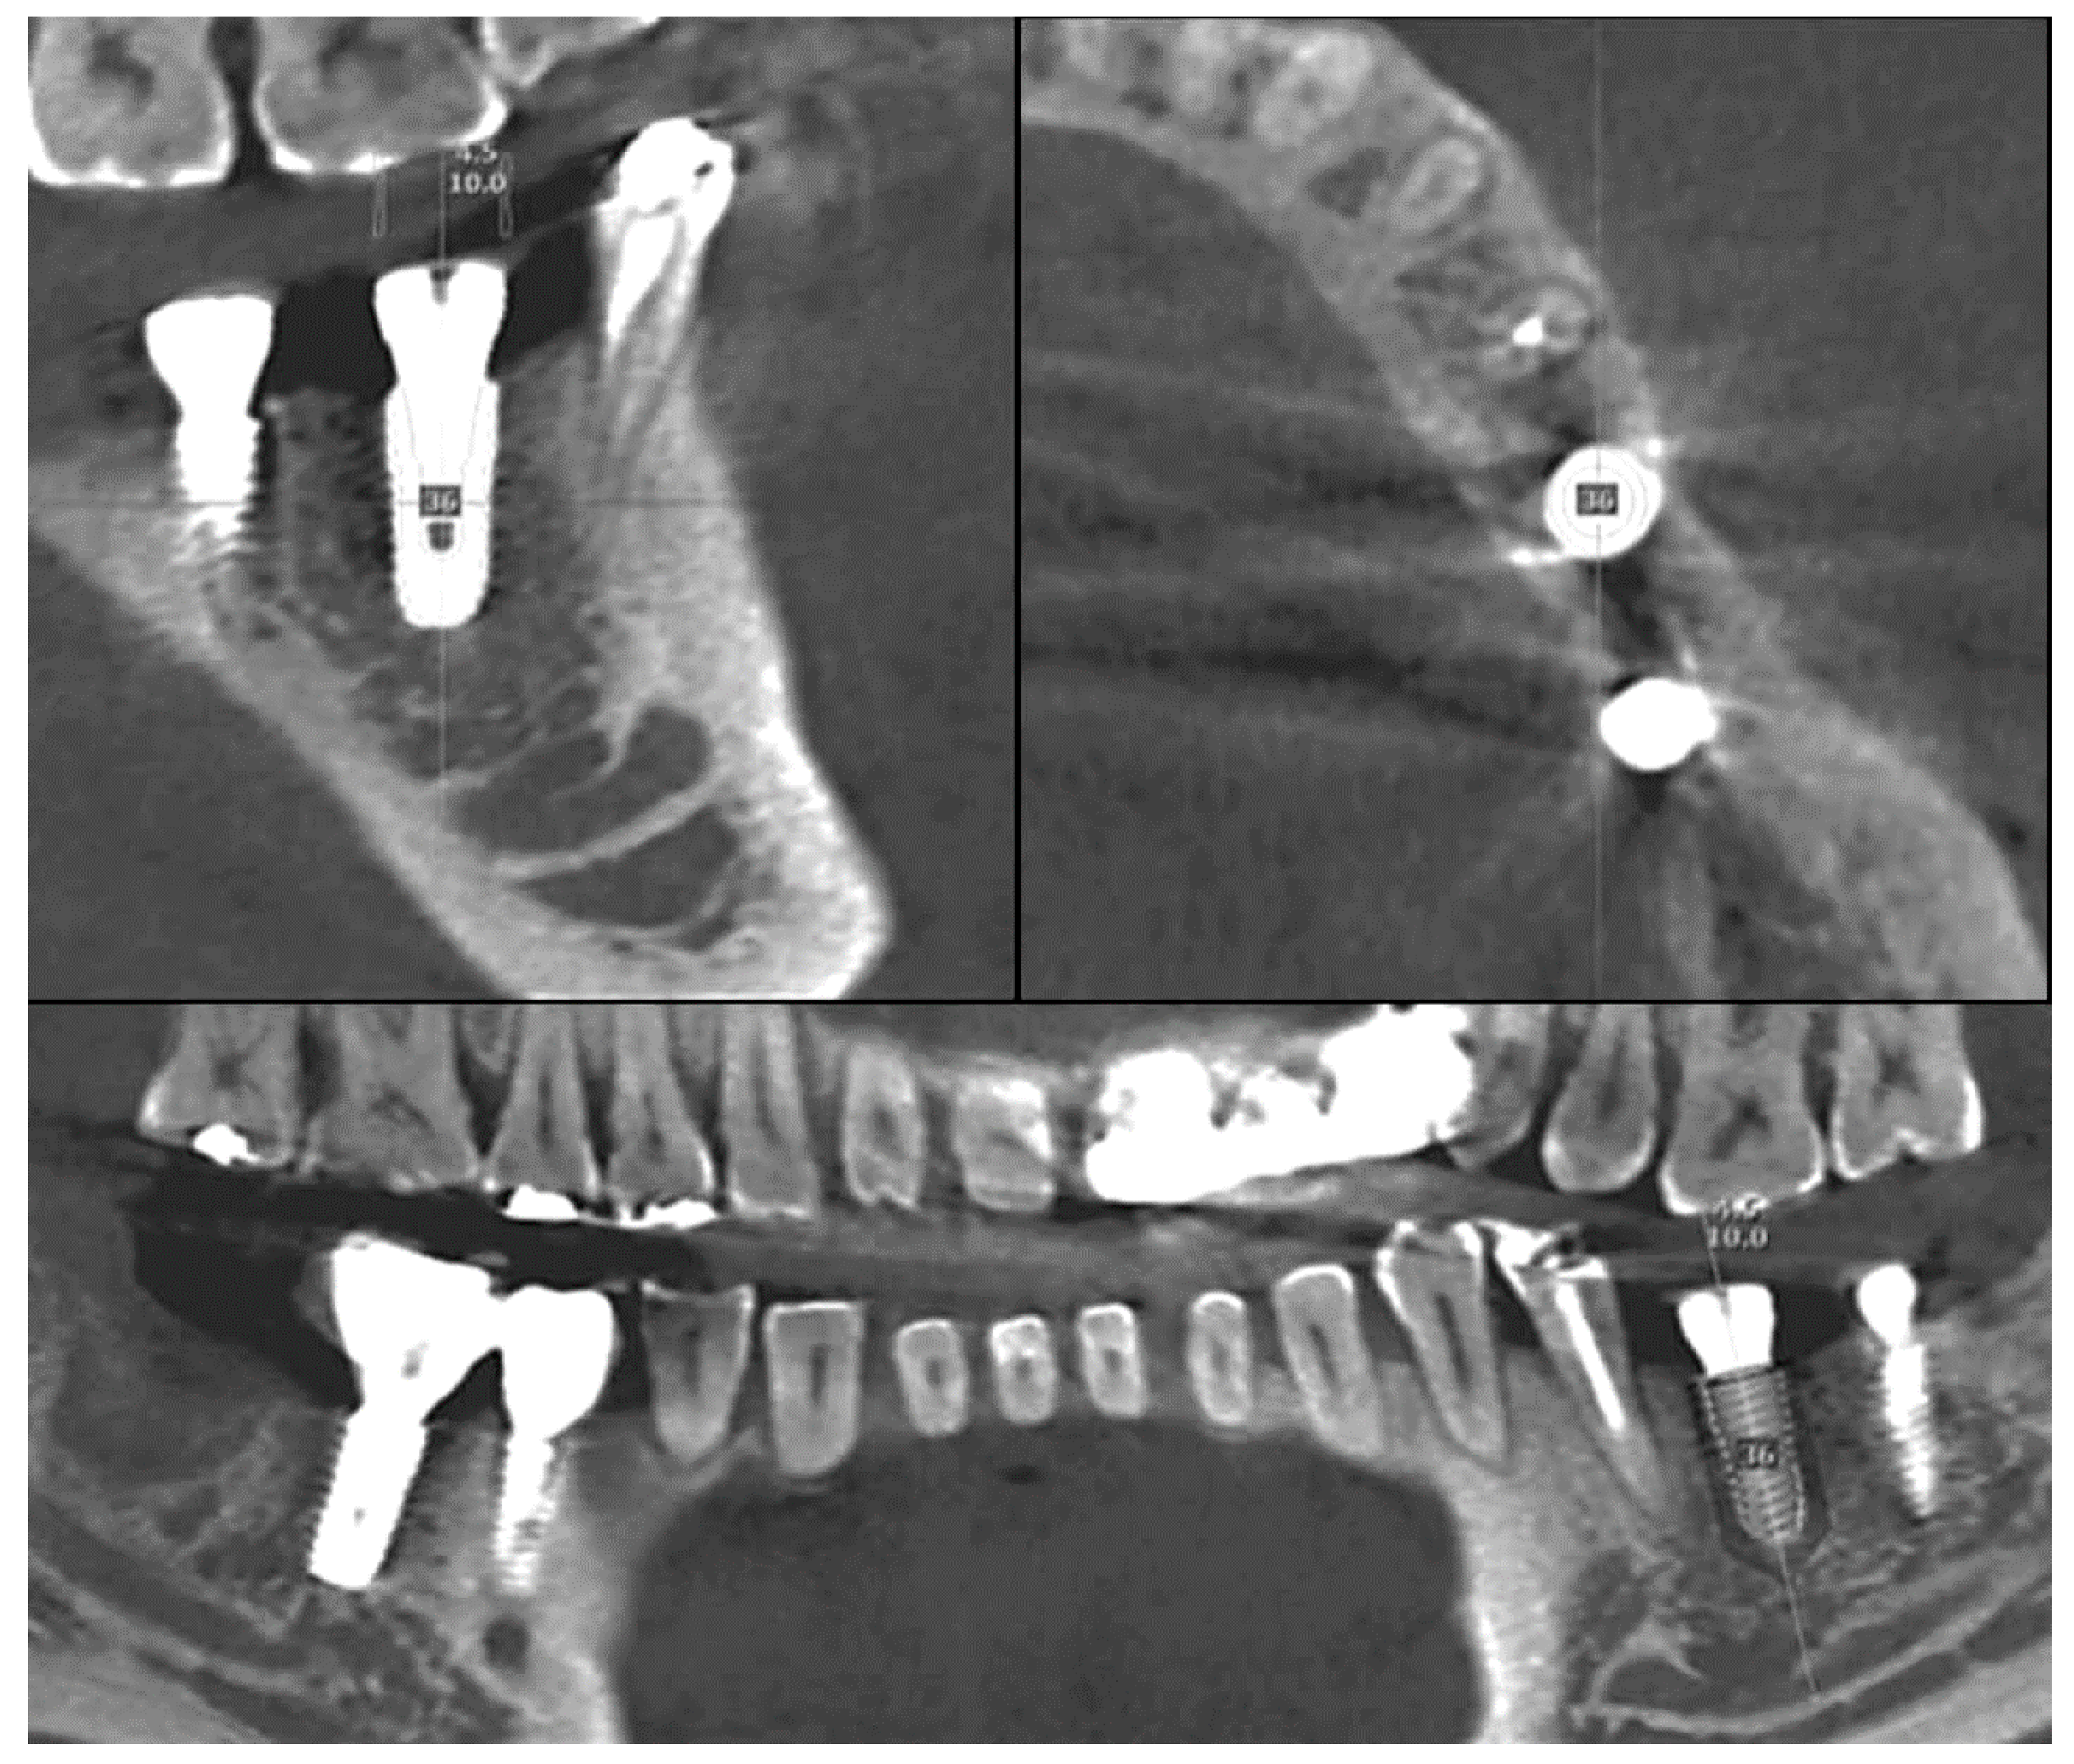

2.1.2. Image Replacing Analysis

Image replacing analysis substitutes implant the CT image with a cross-sectional CT image from the original implant library (Figure 2). Analysis is only possible when the spacing and direction of both of the CT image sections are matched. By overlapping the two images, the actually placed position of the implant can be determined and compared with the planned position.

In Figure 5, information on the planned position was extracted from CT image, because the actual implant position was confirmed by “image replacing analysis” using CT. The reference point and the background data for comparison are all in the CT. Therefore, the accuracy of the superimposition is determined by the resolution of the CT, which consists of a DICOM file.

Figure 2. A library image of implant fixture is loaded on the post-operative CT. By this image replacing analysis, the implant placed position is determined.